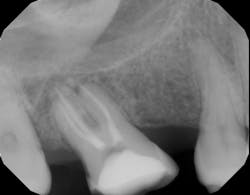

The radiolucency you see in figure 2 is a hole in the bone where inflammation is occurring, but the radiolucency is not the infection. This important concept is often missed: that the radiolucency itself is not the infection; the infection is in the root canal system within the tooth. The radiolucency is just one sign that the root canal is harboring infection. Healing of a periapical radiolucency occurs when the infection level inside the root canal is reduced below a certain threshold and the body has deemed the contents of the root canal as no longer posing a threat. The threshold of what the body feels is a safe level of bacteria is different for each person.